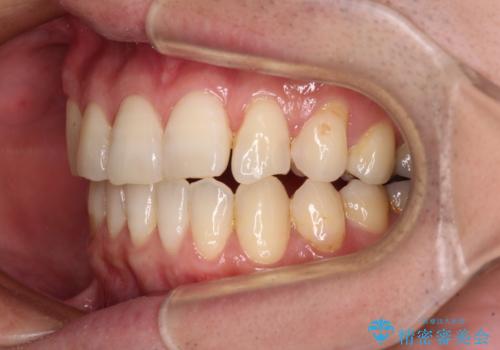

欠損のある歯列 インビザラインで整った歯並びに

- デコボコした前歯をセラミックできれいに揃えたいとのことで来院された患者様です。

歯を削って整えることは簡単ですが、健全な歯を削って後悔してからでは遅いため、矯正治療を提案しました。

はじめは矯正治療の期間が長いことに悩んでいらっしゃいましたが、ある程度整えば満足するだろうとのことで、インビザラインにて矯正治療を行うこととしました。

左上の犬歯が欠損しているため、正中の位置や奥歯の咬み合わせが理想的にならない点を了承していただきました。